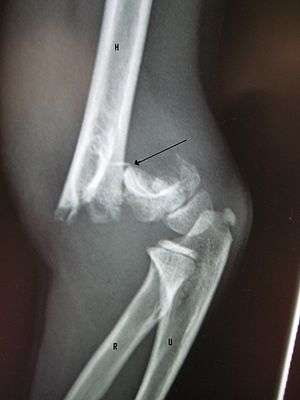

A fracture of the greater tubercle of the humerus

Fracture of the greater tubercle of the humerus

Fracture of the proximal humerus with involvement of the greater tubercle